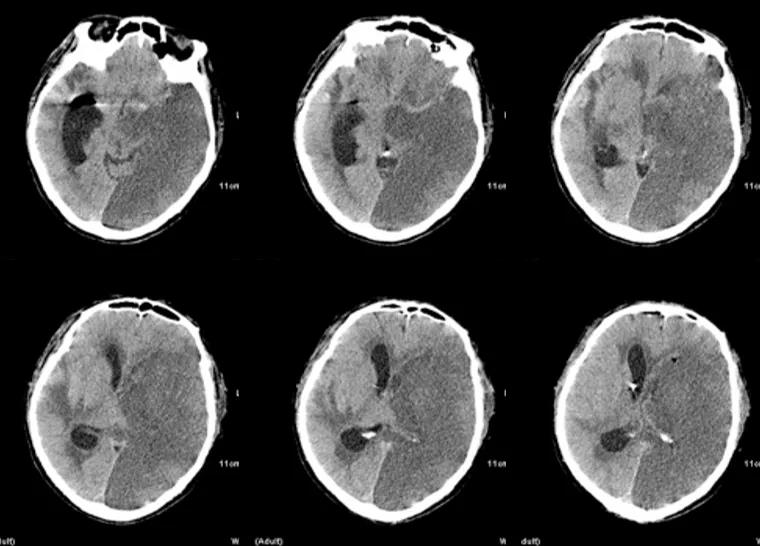

入院时头颅CT(图2):少量蛛网膜下腔出血。

图2. 入院时头颅CT